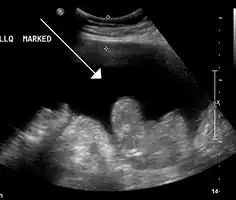

Infection of the peritoneum causes an inflammatory reaction with a subsequent increase in the number of neutrophils in the fluid.[3] Diagnosis is made by paracentesis (needle aspiration of the ascitic fluid); SBP is diagnosed if the fluid contains neutrophils at greater than 250 cells per mm3 (equals a cell count of 250 x106/L) fluid in the absence of another reason for this (such as inflammation of one of the internal organs or a perforation).[8][10] Often the number is greater than 500 cells/uL.[3]

The fluid is also cultured to identify bacteria. If the sample is sent in a plain sterile container, 40% of samples will identify an organism, while if the sample is sent in a bottle with culture medium, the sensitivity increases to 72–90%.[10]